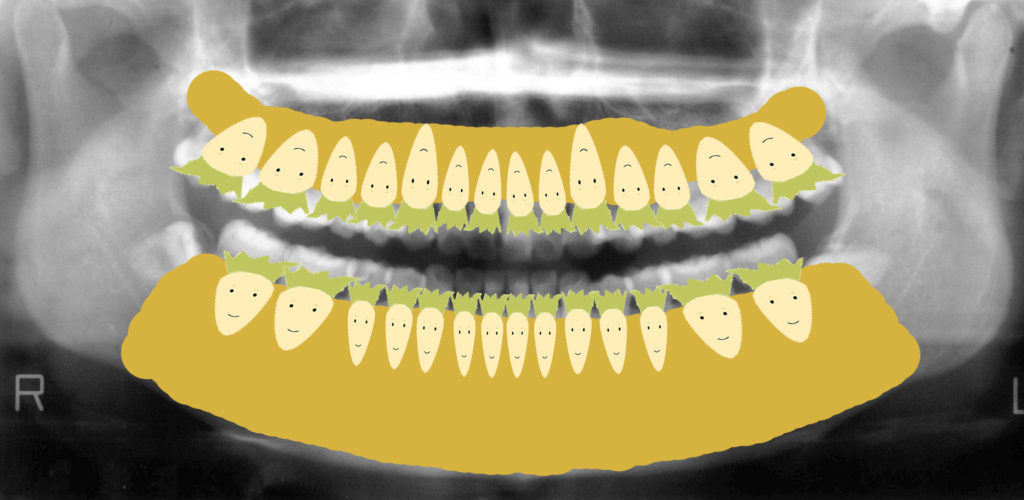

私は患者さんに説明するとき、よく「畑に大根が植わっているイメージ」とお伝えしています。

黄色い部分が畑(土=骨)、白い大根が歯です。

親知らずは隣の歯を圧迫し、どんどん食いつぶしていきます。

放置すると隣の歯もダメージを受けるのです。

畑(骨)に大根(歯)が植わっているイメージ

このレントゲン図をイラストにしてみました。

私はよく患者さんにお話しする時「畑に大根が植わっていると考えて下さい」とお伝えしています。

黄色い部分は畑(骨)です。

白い大根は(歯)です。

下顎の左右に生えていた親知らずは一生懸命大根を食いつぶしていっていますよね。

放置しておくと、どんどんどんどん隣の歯をくいつぶしていってしまいます。